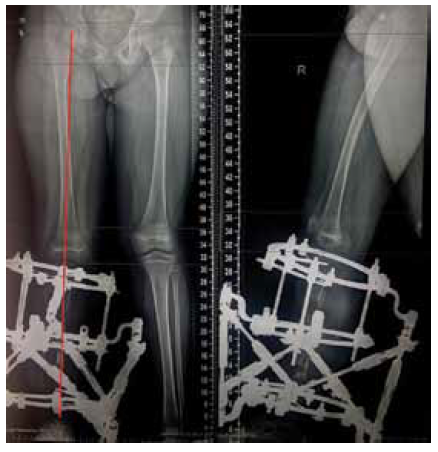

The second stage of treatment was the recommended correction of the resulting multiplane deformities of the affected lower extremity (mMPTA was 94°, mLDTA was 71°, aPPTA was 90°, and aADTA was 59°, shortening the affected lower limb by 8.0 cm). For lengthening and deformity correction of the right lower limb, the patient underwent preoperative planning for deformity correction with the exception of osteotomies in the area of consolidated pseudoarthrosis at the age of 9 years. According to the plan, a two-level osteotomy of the shin bones was performed, as along with lengthening by 5 cm by the Ilizarov method. The deformity was corrected using a repositional unit with Ortho-SUV computer navigation properties. The period of deformity correction was 58 days, and the external fixation period was 247 days. At the end of the fixation period, a recurrence of deformities of the tibial bones was detected with the formation of a deformity apex at the level of the proximal and distal tibial growth zones (mMPTA was 94°, mLDTA was 82°, aPPTA was 86°, and aADTA was 80°) (Fig. 1–4). We applied hemiepiphysiodesis to correct the recurrence of valgus deformity of the tibia. The period of deformity correction was 269 days. The reference angles values of the tibia were within the accepted ranges.

Fig. 4. Roentgenograms of the patient with cCPASB following deformity correction of the bones of the right tibia: а — anterior-posterior view; b — lateral view